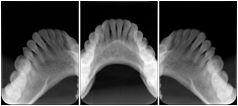

2. A patient requests cosmetic surgery to enhance their facial appearance. The case requires consultation between an orthodontist in New York and an oral surgeon in California. The cephalometric series of 2D projections constructed from a volumetric CT data set that is used for the discussion is arranged by a Structured Display for transfer between the two practitioners.

Cephalometric Series Structured Display

Figure OO-2. Cephalometric Series Structured Display